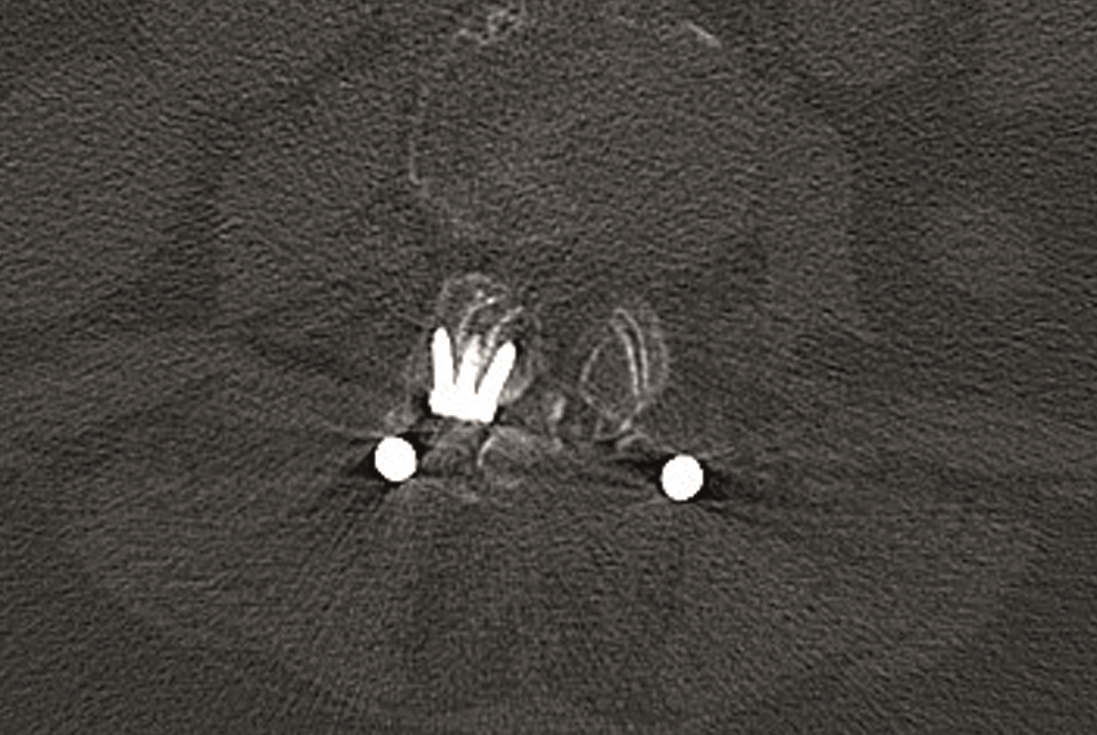

A conventional approach for posterior correction was taken, with indirect Foraminal decompression and Facet Wedge fusion (apex curve). Facet Wedge introduction after curve correction with rod in situ. X-ray follow-up initially (Fig 20), with CT assessment of Facet Wedge fusion after 6 months (Fig 21).

Primary stability and permanent fusion through locking of the facet joints.